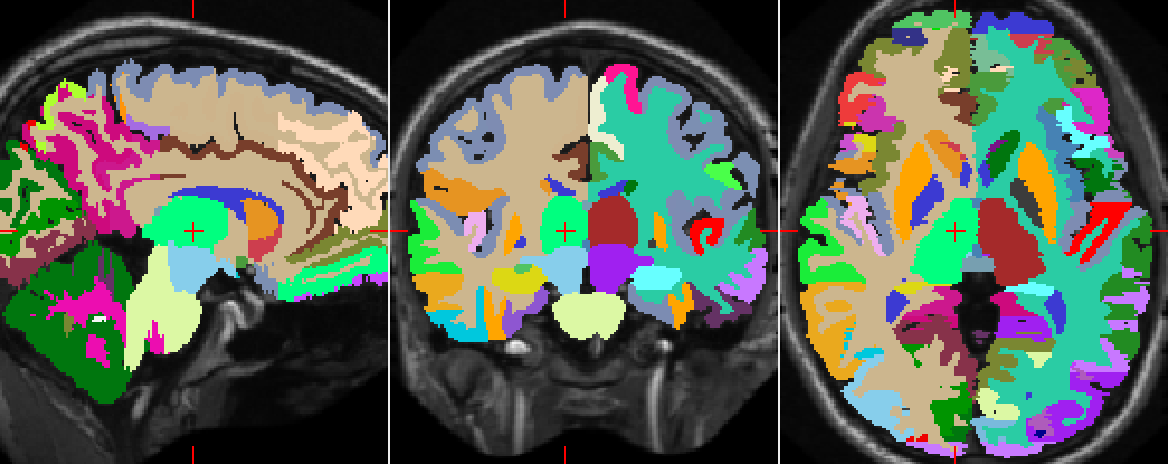

Refer to caption

Figure 5: Example of three orthogonal patches centred on the voxel of interest. Screenshots captured with ITK-SNAP.

We set out to study the performance of SegNet on this dataset despite the fact that deep learning techniques generally require much larger training datasets. All computations had to be run in-memory using a single NVIDIA Tesla K40 GPU with 12GB memory. Therefore we faced a trade-off between the number of datapoints and the number of dimensions of the dataset. On the basis of initial tests, we decided to extract randomly and uniformly across the brain a sample of approximately 202020k voxels from each one of the 151515 atlases, for a total of 300300300k voxels for training purposes, which amounts to only approximatively 1.5%percent1.51.5\% of all the available voxels in the dataset. For each voxel, we extracted a 737773777377-dimensional input vector consisting of a 3D patch of 133superscript13313^{3} voxel intensities (a=13𝑎13a=13), three 2D orthogonal patches of 292superscript29229^{2} voxel intensities (b=29𝑏29b=29), three 2D downscaled patches of size 292superscript29229^{2} containing averaged voxel intensities (the original patch width is 878787 and the scale is 333, i.e. c=29𝑐29c=29, s=3𝑠3s=3) and 134134134 distances to centroids. Figure 5 shows a sample of 2D patches. A validation dataset consisting of 404040k data points was also extracted from the the 15 atlases.

Figure 6 illustrates how well the downscaled patches and the distances to centroids enforce the global spatial consistency of the segmentations. Figure 7 shows the manual and automatic segmentations of a particular MRI. We notice that the misclassified voxels tend to lie on the boundaries of the regions, as expected.